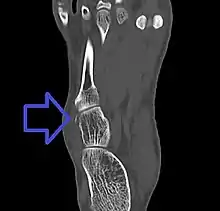

Avulsion fracture of the cuboid on CT

| Avulsion fracture of the right cuboid bone of the foot | |